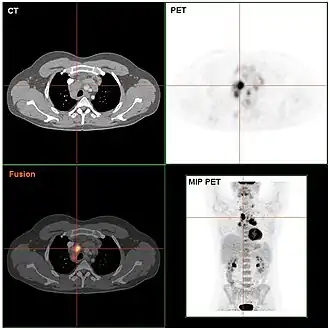

De diagnose wordt gesteld met behulp van microscopisch onderzoek (meestal door meerdere, ervaren pathologen) van een door een chirurg verwijderde lymfeklier (lymfeklierextirpatie). Onder de microscoop wordt bij de ziekte van Hodgkin de typische reed-sternbergcel (RS-cel) gevonden. Hiermee onderscheidt de ziekte zich van alle andere soorten lymfeklierkanker die de verzamelnaam non-hodgkinlymfoom hebben gekregen. De prognose van de ziekte wordt vooral bepaald door het stadium en het subtype van de ziekte. Op grond van een stadiëringsonderzoek worden vier stadia (I t/m IV) onderscheiden naarmate de ziekte zich verder door het lichaam heeft verspreid. Dit onderzoek omvat o.a. een computertomografie, waarbij alle lymfeklieren in de buik- en de borstholte worden afgebeeld, en een beenmergonderzoek.